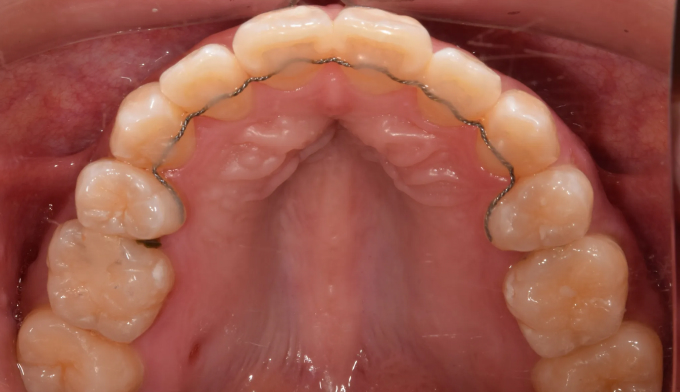

25개월의 교정기간동안 덧니,돌출입, 그리고 개방교합을 해소하였습니다.

그럼에도 돌출감이 조금 남아있어 미니스크류 식립을 동반한 후방이동을 제안하였으나 환자는 현 상태에 만족하여 교정을 조기 마무리한 케이스입니다. 무턱 경향과 입술의 돌출감을 더 해소할 수 있었을텐데 하는 아쉬움이 남습니다. 하지만 항상 교정치료는 환자 입장에서 생각하고 결정해야 합니다. 본인의 얼굴을 스스로가 제일 잘 알기 때문입니다.